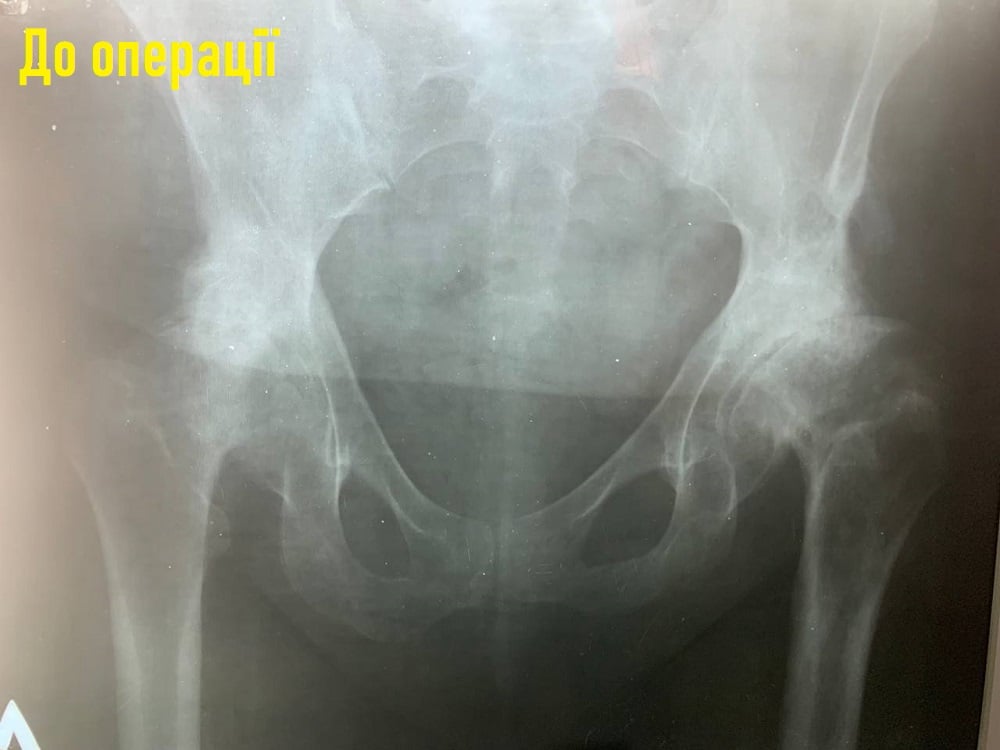

На Волині прооперували 66-річну жінку, у якої вроджений деформувальний артроз кульшових суглобів, який призводить до руйнування суглоба та інвалідності.

До травматологічного відділення звернулася пацієнтка 66 років з двостороннім вродженим деформуючим артрозом кульшових суглобів. Це повільно прогресуюче захворювання, яке призводить до руйнування суглоба та інвалідності.

Жінка в дитинстві була прооперована з приводу двостороннього вродженого диспластичного коксартроза з двох сторін, що звичайно привело до зміни анатомії в даних ділянках та різкого обмеження рухів в обох суглобах.